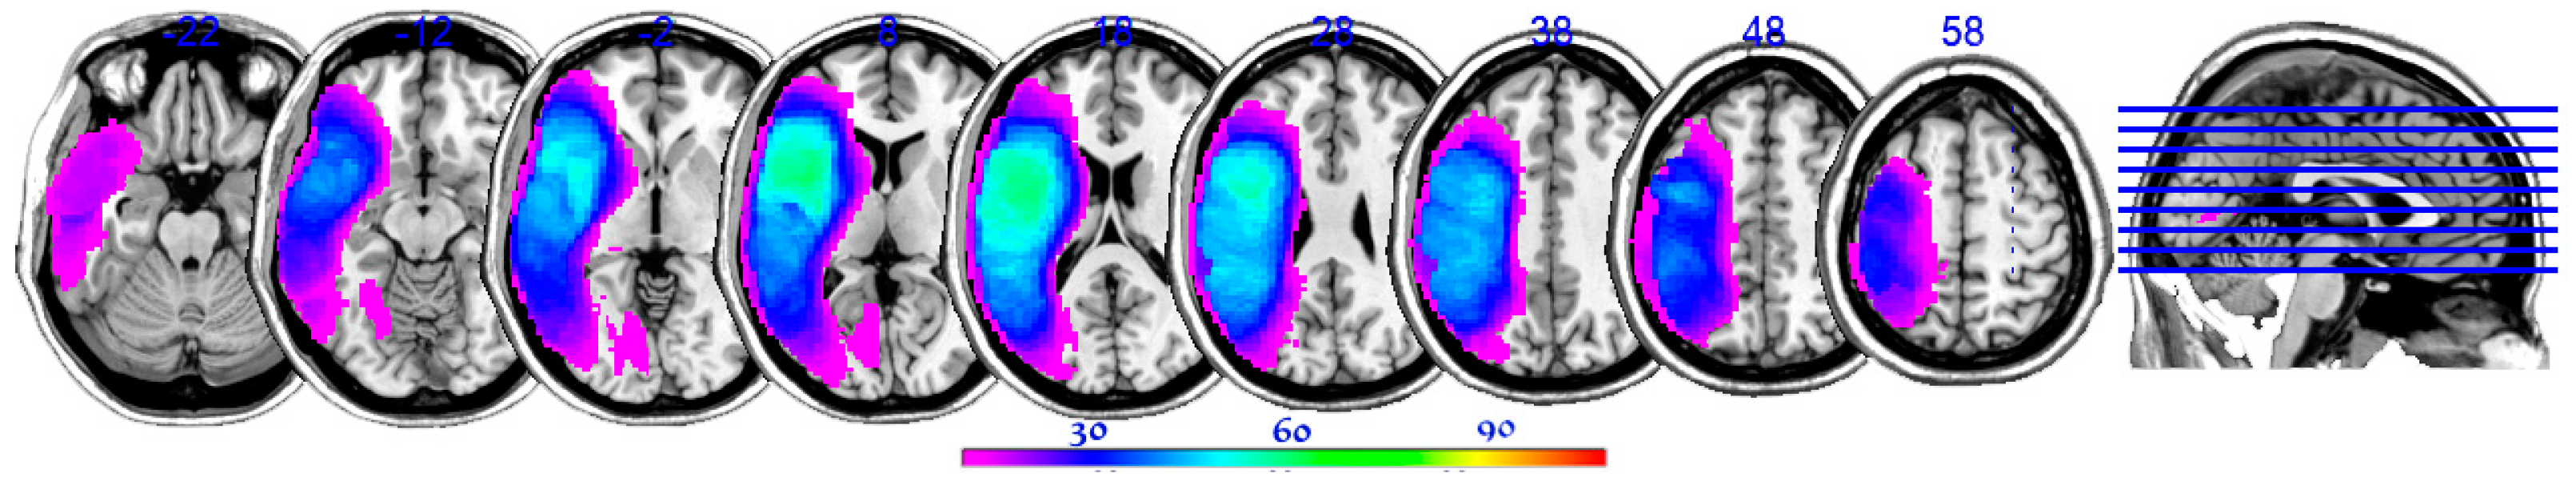

| Subtest | Volume | Px | Py | Pz | Min T | Max T |

|---|---|---|---|---|---|---|

| Complex | 614 | −24 | −30 | 62 | 3.60 | 5.89 |

| Instrumental | 356 | −14 | −44 | 58 | 3.61 | 5.99 |

| Facial | 88 | −50 | −34 | −20 | 3.67 | 5.58 |

| Upper limb | 68 | −72 | −16 | 2 | 3.57 | 5.1 |